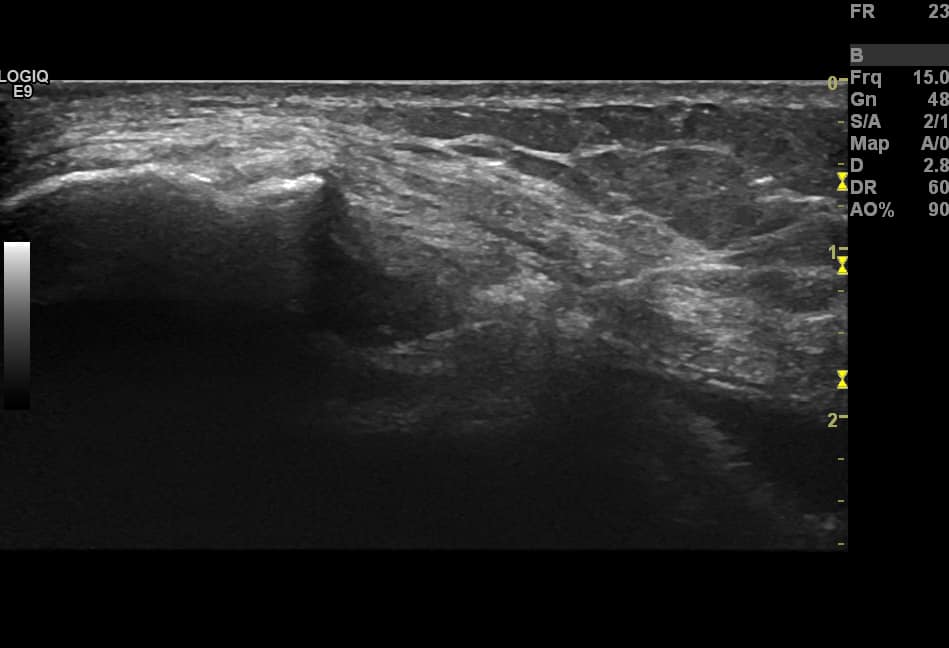

Us Guided Knee Injection Point of care ultrasound can accurately determine the presence of a joint effusion as well as guide synovial fluid aspiration 1 The suprapatellar bursa the largest communicating bursa of the knee joint allows for a location that is easily visualized with ultrasound and can be rapidly and safely accessed for joint arthrocentesis

An overview of the scanning technique for ultrasound guided knee injection including critical anatomy and needle path Visit http www sonosite educati The anatomy of the knee is particularly amenable to ultrasound US imaging and therefore most knee structures can be accurately targeted using US guidance In most individuals these structures are superficial and the overlying soft tissues are a prior landmark guided LG knee joint injection complex postoperative or Disclosure The

US Guided Injection of the Knee Injection of the non effusive knee dry knee is the most common intra articular needle procedure in medicine and thus dominates in a MSK practice The knee can be effectively injected with US guidance from the supine straight leg lateral suprapatellar